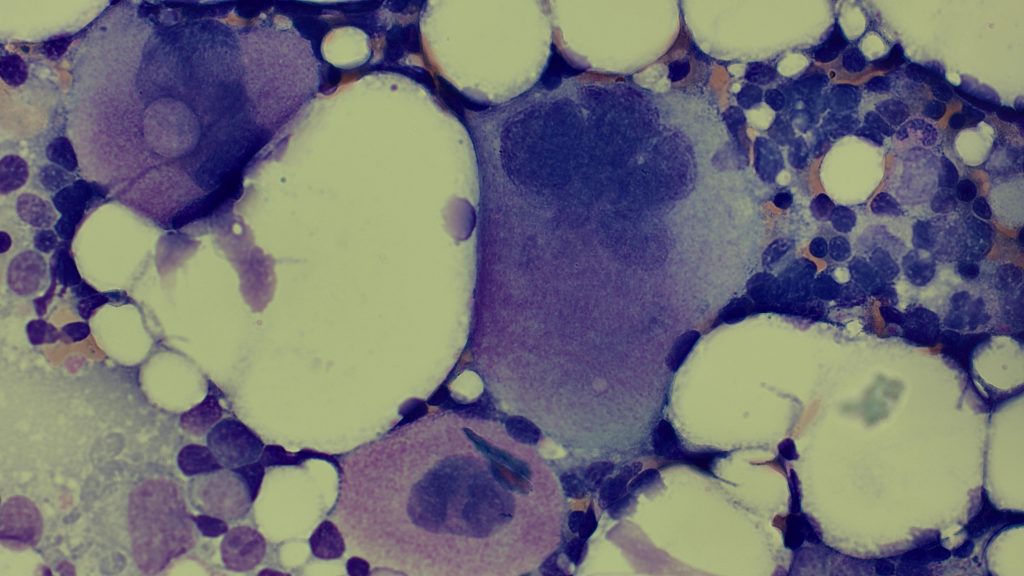

Iron staining